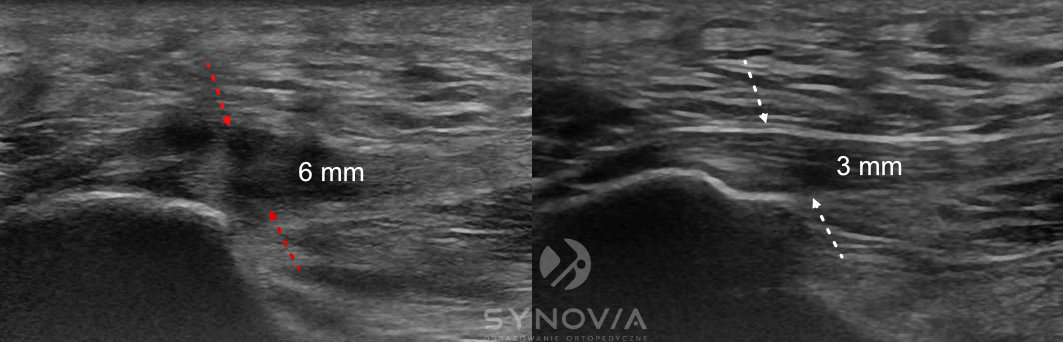

USG

Co widać: Pogrubienie powięzi >4mm, zmiana echostruktury, hipoechogeniczne obszary obrzęku, wzmożone unaczynienie w badaniu dopplerowskim.

MRI

Co widać: Szczegółowa ocena powięzi, obrzęk szpiku kostnego w kości piętowej, przydatne w różnicowaniu przyczyn.